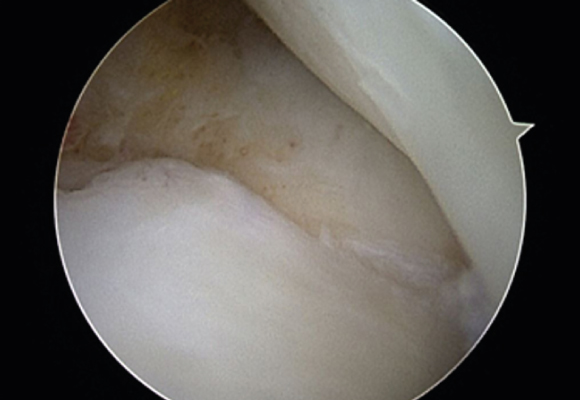

연골판봉합술

혈관이 있는 부위에 파열이 발생한 경우 연골판을 봉합해 주는 수술 시행

ㆍ환자 동의를 받은 자료이며, 이미지 사진은 실물과 다를 수 있습니다. (22.06.09)